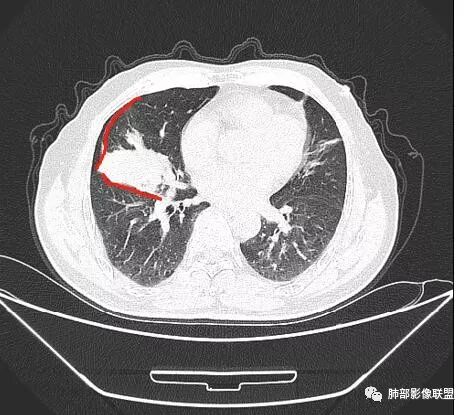

我们现在看主病灶,病灶紧贴叶裂:

我想看冠状位,就是看它长轴、病灶的整体形态

外围大、内带小

这时候我认为支气管最重要

支气管进入其中,远端粘液栓

我认为鉴别:结核?腺癌?

吴婧老师和南边老师都对该病例进行了深入分析。从支气管管壁的增厚,支气管狭窄后扩张,支气管粘液栓,病灶形态,到病灶不均匀强化及坏死彻底,到周边病灶及肺组织空气的潴留,加之纵隔内淋巴结肿大伴钙化等等,都支持慢性炎性病灶,尤其是结核。